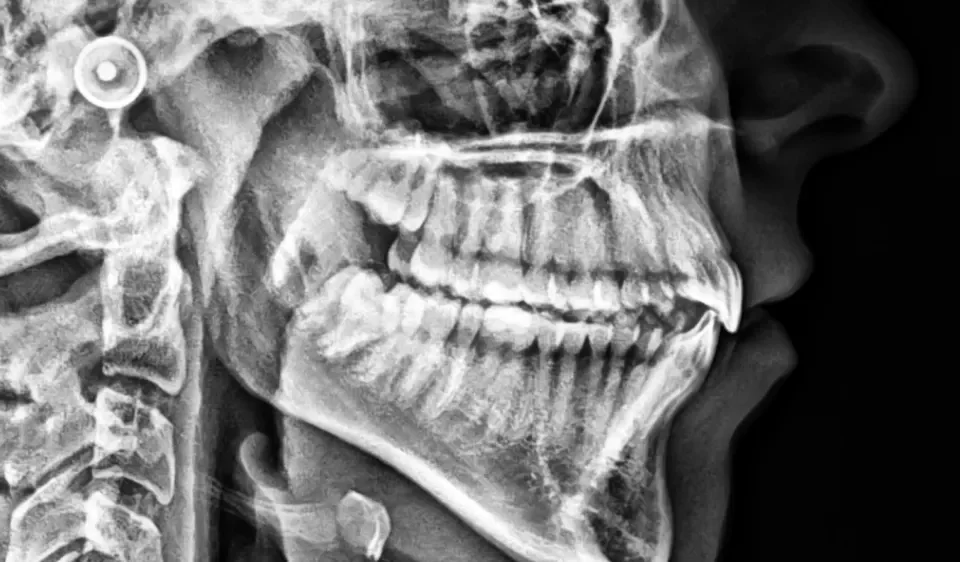

Aparat RTG pokazuje cień. Tomografia CBCT 3D pokazuje trójwymiarowy model – kanały korzeniowe, kość pod implant, stawy żuchwowe i oba łuki jednocześnie. Jeden aparat. Cztery wyspecjalizowane badania. Wynik gotowy tego samego dnia.

Tomografia CBCT 3D tworzy trójwymiarowy model uzębienia, kości, stawów i zatok. Lekarz ogląda każdą strukturę z dowolnej strony i w dowolnym przekroju – bez nakładania tkanek na siebie jak na zwykłej panoramie OPG. To nie jest lepsza wersja RTG – to inny wymiar informacji.

CBCT nie jest badaniem rutynowym. Zlecane jest wtedy, gdy zwykłe zdjęcie nie daje danych wystarczających do decyzji – np. przed wszczepem implantu, przy trudnym leczeniu kanałowym, diagnostyce stawów żuchwowych lub planowaniu leczenia ortodontyczno-chirurgicznego. W OrtoRodzina badanie realizowane jest na miejscu, bez odsyłania do zewnętrznej pracowni. Wynik w dniu badania. RTG panoramiczne OPG pozostaje pierwszą linią diagnostyki – CBCT uzupełnia je, gdy dane 2D nie wystarczą.

OPG to projekcja płaska – wszystkie struktury jamy ustnej rzutowane są na jeden obraz; struktury leżące przed sobą i za sobą nakładają się. CBCT rejestruje trójwymiarowy model: każda struktura ma swoje miejsce w przestrzeni i jest widoczna bez nakładania na sąsiednie elementy. OPG jest szybszym, niskonakładowym badaniem przesiewowym – zalecane jako pierwsza diagnostyka obrazowa przed zdecydowaną większością procedur. CBCT stosowane jest jako kolejny krok, gdy dane 2D nie są wystarczające do podjęcia decyzji klinicznej: precyzyjne planowanie implantu, diagnostyka kanałów korzeniowych, ocena stawów SSŻ lub wad szkieletowych to typowe wskazania nieobsługiwane przez OPG.